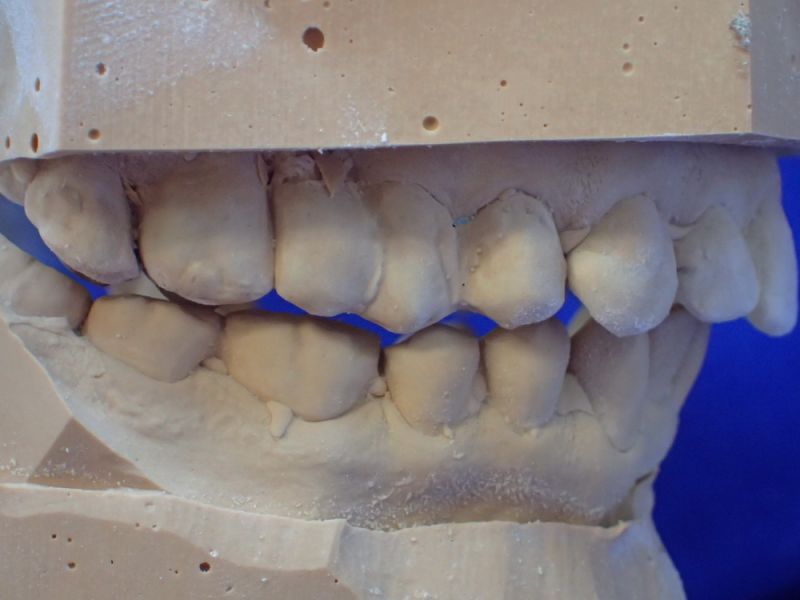

Erkennbar ist die massive Abweichung der habituellen Bisslage von der neuromuskulär zentrierten Bisslage.